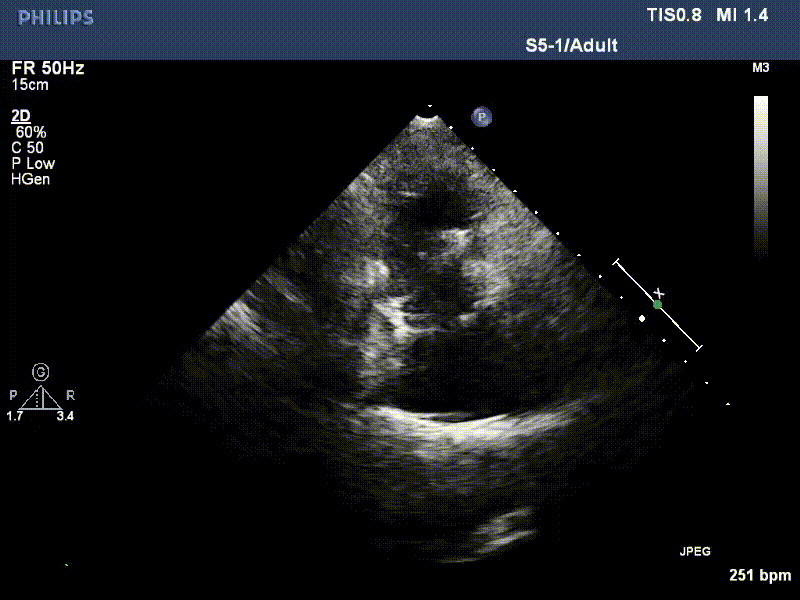

近日,復(fù)旦大學(xué)附屬中山醫(yī)院葛均波院士、周達(dá)新教授團(tuán)隊,聯(lián)合心外科王春生、魏來主任,麻醉科繆長虹、郭克芳主任,于2021年11月14日進(jìn)行多學(xué)科聯(lián)合救治的兩例極重度三尖瓣反流的患者,完成了一年的隨訪工作。目前患者身體恢復(fù)良好,狀態(tài)極佳。隨訪心臟超聲提示LuX-Valve Plus人工三尖瓣瓣架固定穩(wěn)定,無三尖瓣反流和瓣周漏。此次LuX-Valve Plus的1年成功隨訪體現(xiàn)了葛均波院士團(tuán)隊在三尖瓣介入治療研究領(lǐng)域的領(lǐng)先地位及不斷探索的精神,也進(jìn)一步驗證了LuX-Valve Plus經(jīng)血管三尖瓣置換系統(tǒng)的臨床安全性和有效性。

1年前,兩例患者因難治性雙下肢水腫輾轉(zhuǎn)多家醫(yī)院尋求救治,考慮到兩例患者高齡、基礎(chǔ)疾病多、STS評分高,不適合傳統(tǒng)外科開胸手術(shù),葛均波院士及其團(tuán)隊周達(dá)新教授、潘文志教授、張源博士、陳莎莎博士、陳丹丹博士聯(lián)合心外科王春生、魏來主任,麻醉科繆長虹、郭克芳主任以及心超室的潘翠珍教授、李偉教授共同討論決定,采用我國創(chuàng)新器械LuX-Valve Plus經(jīng)血管三尖瓣置換系統(tǒng)為患者進(jìn)行手術(shù)。相較于第一代產(chǎn)品LuX-Valve,LuX-Valve Plus經(jīng)血管三尖瓣置換系統(tǒng)對輸送系統(tǒng)進(jìn)行了全面升級,實現(xiàn)了經(jīng)頸靜脈入路的方式,進(jìn)一步減小了手術(shù)風(fēng)險和對患者的創(chuàng)傷。目前隨訪1年心超結(jié)果顯示,三尖瓣極重度反流消失,人工三尖瓣瓣膜穩(wěn)定牢固,瓣葉活動度良好,右心室及下腔靜脈明顯縮小,心輸出量增加。兩位老人手術(shù)后沒有出現(xiàn)過胸悶氣促的癥狀,下肢水腫緩解,活動耐力提升,生活質(zhì)量也大為提高。

圖2 患者植入LuX-Valve Plus后,1年隨訪心超提示無三尖瓣反流